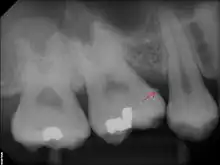

The following minerals are detectable in calculus by X-ray diffraction:

- brushite (CaHPO4 · 2 H2O)

- octacalcium phosphate (Ca8H2(PO4)6 · 5 H2O)

- magnesium-containing whitlockite (Ca9(Mg,Fe)(PO4)6(PO3OH))

- carbonate-containing hydroxyapatite (approximately Ca5(PO4)3OH but containing some carbonate).[16]

Subgingival calculus forms below the gumline and is typically darkened in color by the presence of black-pigmented bacteria,[18] whose cells are coated in a layer of iron obtained from heme during gingival bleeding.[19] The reason fossilized bacteria are initially attracted to one part of the subgingival tooth surface over another is not fully understood. However, once the first layer is attached, more calculus components are naturally attracted to the same places due to electrical charge. This is because the calcium phosphate salts contained in them exist as electrically unstable ions (unlike calcium phosphate, the primary component of teeth). The fossilized bacteria pile up rather haphazardly, while free-floating ionic components (calcium phosphate salts) fill in the gaps.[15]